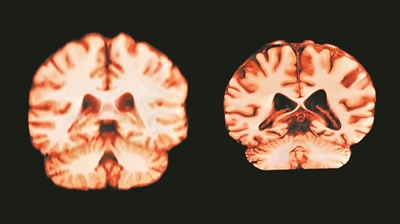

健康大脑(左)和受阿尔茨海默病影响的大脑。

图片来源:英国《自然》杂志网站